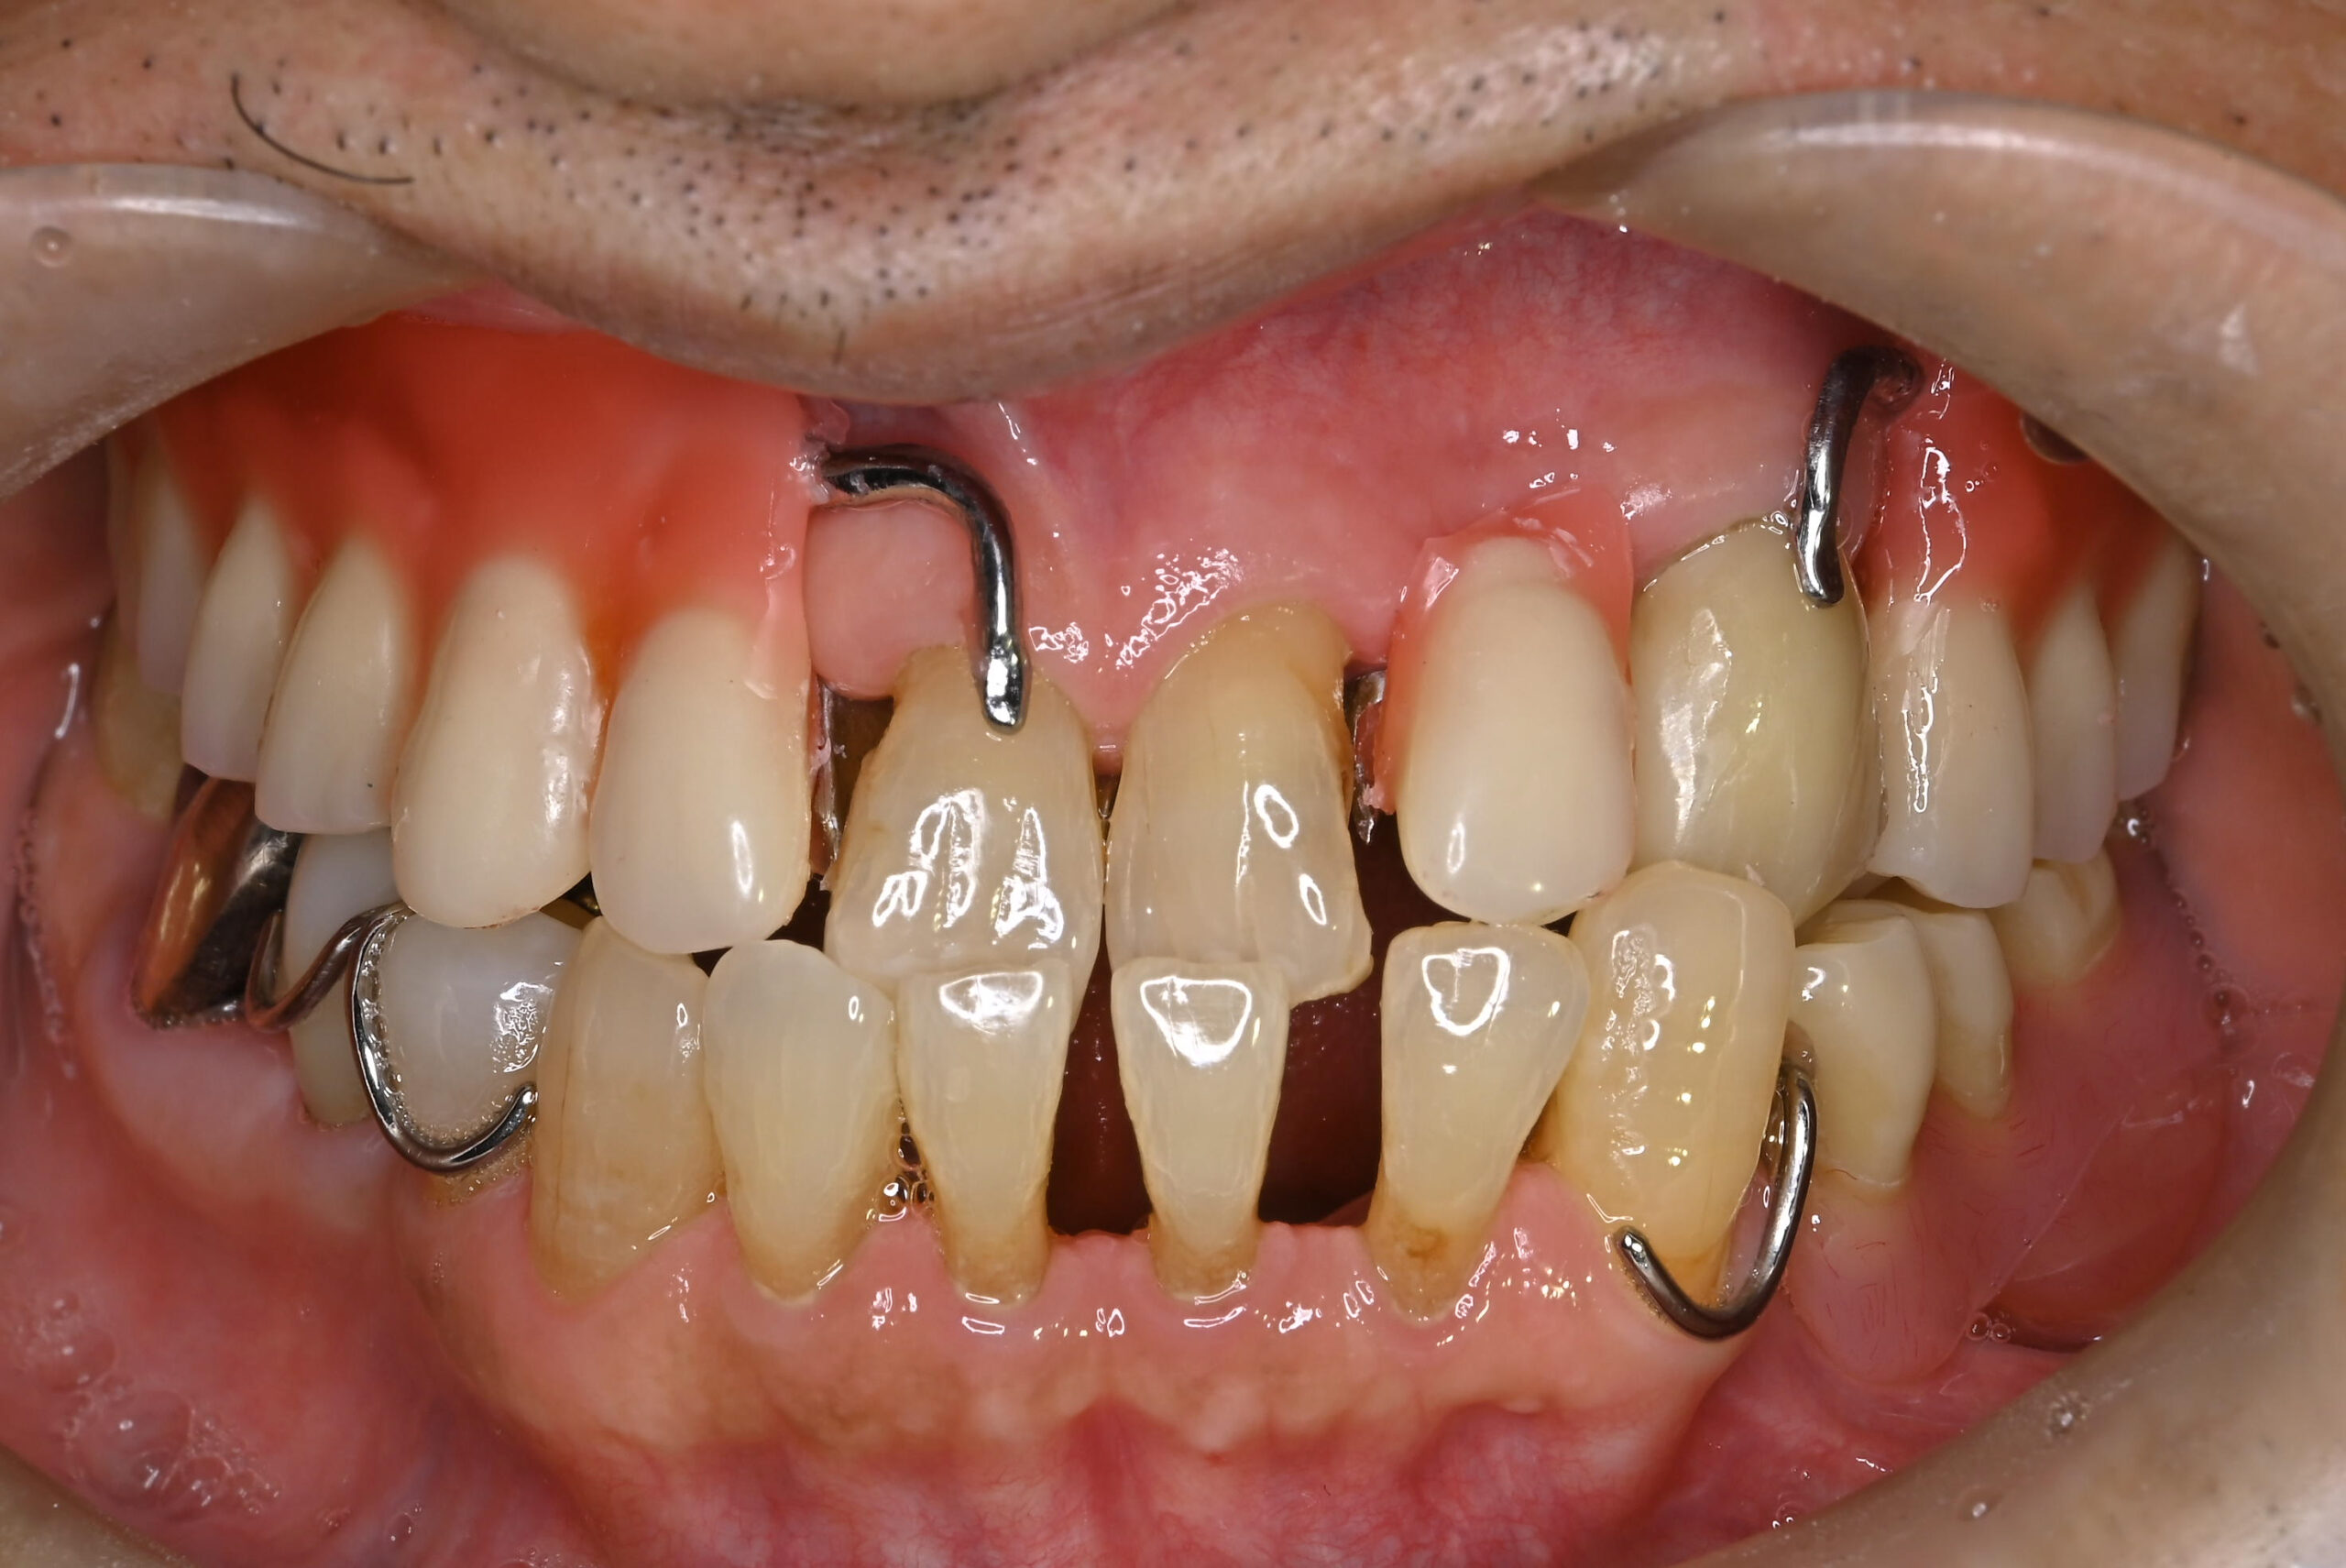

治療前写真3(口腔内写真)

-

【症例】40代で「総入れ歯」と宣告された絶望からの回復

重度の歯周病により、他院で「総入れ歯にするしかない」と診断された40代の男性のケースです。

「まだ若いのに、会話中に外れるかもしれない恐怖と一生付き合うのか」患者様はそんな深い絶望を抱えて当院に来院されました。